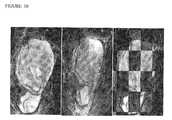

FIG. 10 shows co-registration of MRI studies in soft tissue sarcoma. A) Fat-suppressed T2-weighted image of pelvic liposarcoma prior to treatment. B) Overlay of post- and pre-treatment scans based only on rigid body structures shows distortion of the tumor because of increases in volume over time. C) Checkerboard display of alternating images from pre- and 7-week post-treatment studies after post-processing using mutual information and warping shows precise registration of anatomic features within the tumor for subsequent PRM analysis.

This example describes whole tumor and PRM analysis of ADC and DCE-MRI data in soft tissue sarcoma. As proof-of-principle that PRM analysis enhances detection of therapy-induced changes in soft tissue sarcoma, diffusion and DCE-MRI was performed on a patient undergoing neoadjuvant chemotherapy with doxorubicin and ifosfamide. MRI studies after 1 and 7 weeks of therapy were co-registered with the pre-treatment examination. The use of warping registration methods accounted for the increase in tumor volume during neoadjuvant chemotherapy, as seen by precise alignment of pre- and 7-weeks post-treatment tumors on the checkerboard display (FIG. 10) (see, e.g., Meyer CR, et al., Med Image Anal. 1997; 1: 195-206; Kim, et al., Proc. Intl. Soc. Mag. Reson. Med. 8 (2000) 1765; Meyer, CR, (2006) Molecular Imaging 5(1):16-23; Kim, B, et al., (1997) NeuroImage 5(1):31-40; Collignon, A, et al., (1995) Lecture Notes in Computer Science 905: 195-204; Viola, P, et al., (1995) Alignment by maximization of mutual information, in Proceedings of 5thInt'l. Conf. on Computer Vision, MIT, IEEE Press 95CH35744: 16-23; Bookstein, FL (1989) IEEE Transactions on Pattern Analysis and Machine Intelligence 11(6):567-585; Jacobs, M, et al., (1999) Medical Physics 26(8):1568-1578; Pelizzari, CA, et al., (1987) J. Nucl. Med. 28(4):683; Besl, P J, et al., (1992) IEEE Trans. Pattern Analysis and Machine Intelligence 14(2):239-256; Lazebnik, R, et al., IEEE Trans Med Imaging 22(5):653-660; Breen, M, et al., J Mag Res Imag 18:90-102; Wilson, D, et al., (2004) M Breen, R Lazebnik, S Nour, J Lewin (2004) Radiofrequency thermal ablation: 3D MR histology correlation for localization of cell death in MR lesion images, in Proceedings of Internat Symp Biomed Imaging, Arlington, Va.: 1537-1540; Zarow, C, et al., J Neuorsci Methods 139:209-215; Park, H, et al., M Piert, A Kahn, R Shah, H Hussain, J Siddiqui, C Meyer (2008) Registration methodology for histological sections and ex vivo imaging of human prostate, Academic Radiology (accepted for publication); each herein incorporated by reference in their entireties). Using these co-registered images, therapy-induced changes in ADC and Ktrans by whole-tumor mean values and PRM of spatially-localized changes in these parameters within the tumor was analyzed.